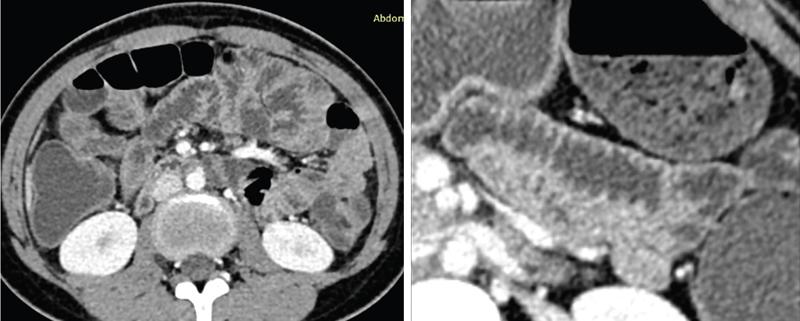

Computed tomography

CT enterography

CT enteroclysis